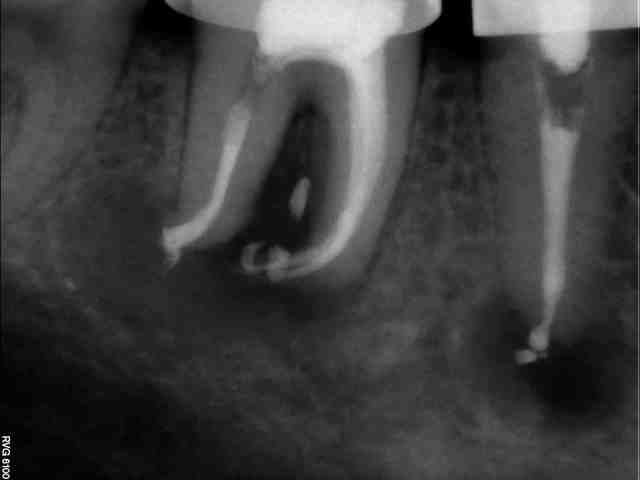

Bon...on va attendre 6 mois avant de dire qu'il n'y a pas de soucis. La difficulté ici était le lentulo fracturé coronairement qui n'autorisait pas le by-pass (au départ, parce que je lui ai expliqué qu'il fallait qu'il se pousse pour me laisser passer et il a été gentil, il m'a obéit :-))

En fait, ça ne se voit pas sur la radio d'eugenol (perte de qualité) mais il y a un lentulo dans l'obturation du canal MV (et un autre au niveau apical que l'on voit ici).

Pour répondre à dumaille : oui. Si tu regardes bien la radio postop, tu verras des trabécules osseuses juste sous la furcation. Le sondage était normal aussi bien en lingual qu'en vestibulaire. La lésion étant fermée, il n'y a aucune raison qu'en cas de succès apical il y ait une persistance radioclaire entre les racines.

Pour Aymen : Une fois le by-pass réalisé, Dominique Martin conseillait il y a quelques années dans une conférence de la SOP de rester en manuel avec les instruments NiTi. Je ne sais pas s'il s'applique ça à lui même ou si c'était un conseil destiné aux praticiens lambdas. Personnellement, je prend souvent ce risque (si je sens intuitivement en fonction du cas que je peux le faire, et si j'ai le moindre doute, je pense à mon ami Willy qui me disait un jour "si tu te poses la question, ne le fais pas !" Je pense d'ailleurs souvent à lui à cause de ça car il y a plein de situations cliniques où je me pose des questions. Dans le cas présenté, j'y suis allé en rotation mécanique justement. L'instrument fracturé coronairement à été enlevé après la mise en forme. Il faut bien comprendre qu'ici, ce fragment était un lentulo. Si ça avait été un protaper F2 par exemple, je serai sans doute rester en manuel, en fonction des sensations tactiles avec le dernier instrument acier utilisé (ici une lime K15).

Pour l'obturation, je ne vois aucune raison de changer quoique ce soit à cause d'un fragment d'instrument qui resterait en place. Une technique à chaud me parait cependant idéale pour enrober le fragment. Dans le cas présent, c'était thermafil et la courbure apicale en était une excellente indication à mon avis.